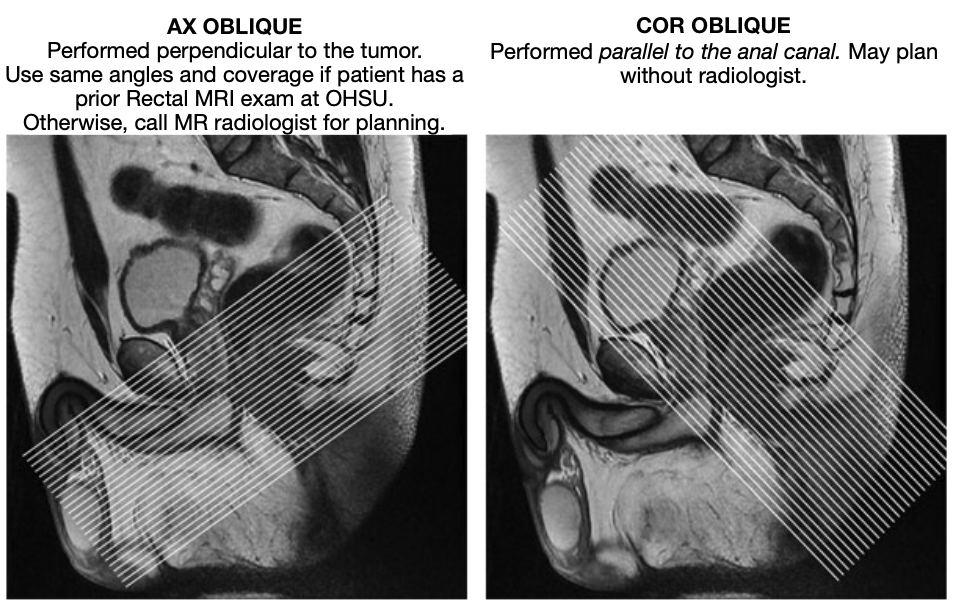

From www.vrogue.co

Rectal Cancer Protocol Mri Radiology Reference Articl vrogue.co What Is A Mri Protocol Mri allows the acquisition of images with excellent tissue contrast and. Magnetic resonance imaging, or mri, is a noninvasive medical imaging test that produces detailed images of almost every internal structure in the human body, including the organs,. When you put a patient in a strong. Mri protocols are a combination of various mri sequences, designed to optimally assess a. What Is A Mri Protocol.